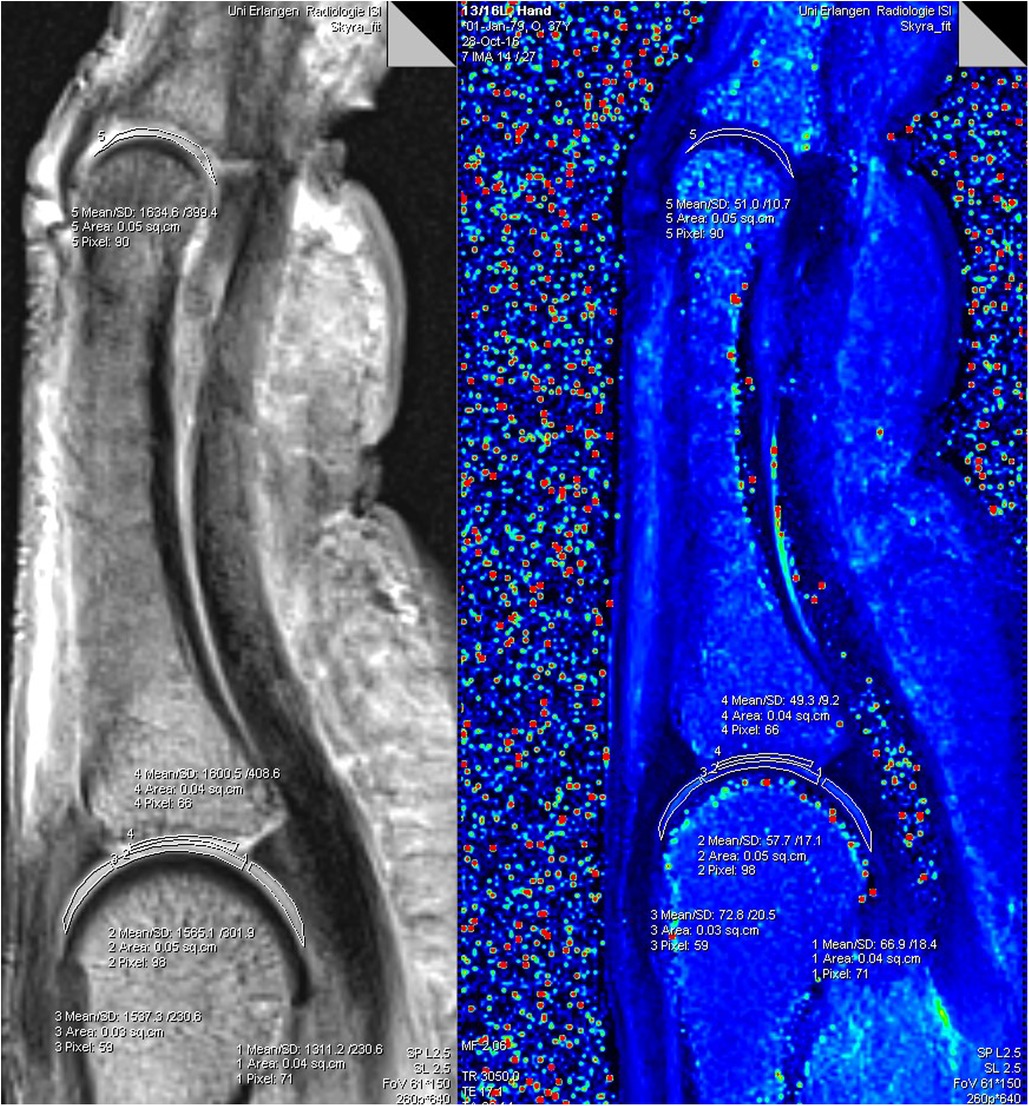

![]() | Evaluation of finger cartilage composition in recreational climbers with 7 Tesla T2 mapping magnetic resonance imaging“No negative impact on cartilage composition due to the sport activity was found, whereas age-related effects on the cartilage seemed to be more prominent.”Learn More |